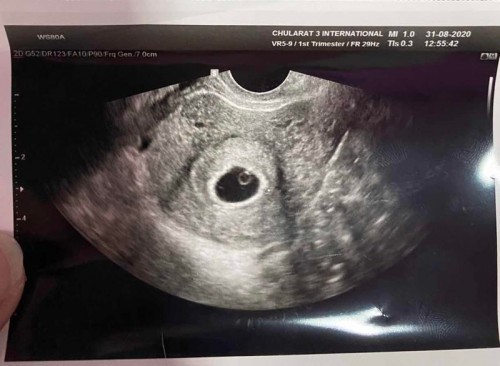

ตั้งครรภ์ได้ 8 week หมอซาวด์ไม่เห็นเด็ก เศร้าเลยค่ะ

ที่เป็นกลมๆในถุงตั้งครรภ์ไม่ใช่เด็กหรอคะ นี้ภาพซาวด์ของเค้า หมอบอกว่าเป็นเด็กแค่ยังไม่เห็นหัวใจเพราะอายุครรภ์ยังน้อย

ขออนุญาติตอบตามประสบการณ์ตัวเองนะคะ ตอนเราท้องลม เราก็เคยถามหมอค่ะ ว่าในถุงคืออะไร หมอบอกว่าเหลือแต่ถุงไข่แดงค่ะ (เราสังเกตว่าจะอยู่ติดขอบถุงตั้งครรภ์) อีกอย่างถุงตั้งครรภ์จะโตตามอายุครรภ์ เมื่อถึงช่วงนึงร่างกายจะรับรู้เองค่ะว่า ในถุงไม่มีอะไร และจะเริ่มมีเลือดออกค่ะ เป็นกลไกปกติของร่างกายค่ะ สุดท้ายเราเลือดออกและขูดมดลูกค่ะ และตอนนี้ท้องใหม่แล้ว น้อง 28 สัปดาห์แล้วค่ะ